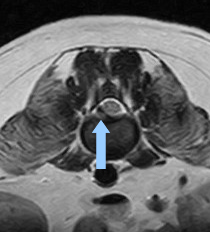

症例③ 胸腰部椎間板ヘルニア

急に後肢が立てなくなったため来院

| レントゲン検査 | 胸腰椎椎間板の石灰化 |

| 胸腰部MRI検査 | 重度の椎間板逸脱がみとめられた |

| 診断 | 胸腰椎椎間板ヘルニア(グレードⅢ) |

| 治療 | 外科的治療、リハビリテーション |

![]() MRI(横断面) |